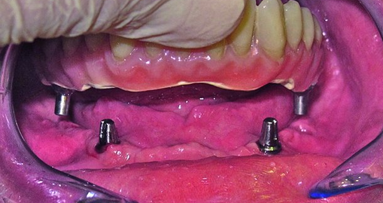

Après avoir examiné les différents problèmes avec la patiente, celle-ci avait décidé qu’une prothèse amovible supra-implantaire stabilisée par deux implants, représentait le meilleur choix de traitement et aussi le moins compliqué pour elle. La prothèse maxillaire ne lui posait pas de problème vu qu’elle était rétentive et stable, et pour limiter les coûts, celle-ci n’a donc pas été remplacée. Un guide chirurgical a été fabriqué après correction de la dimension verticale et des paramètres tant esthétiques que phonétiques, au moyen d’une prothèse d’essai en cire. Deux implants de liaison (Straumann), diamètre d’épaulement de 4,1 mm et longueur de 8 mm, ont été placés aux positions dentaires 32 et 42 (Figs. 7a et 9b). Après un délai de trois mois pour permettre l’ostéointégration, une prothèse amovible stabilisée par des piliers-boules a été posée. Cette prothèse n’a présenté aucun problème prothétique ou chirurgical durant cinq ans. Malheureusement, la patiente a revu son denturologiste et une tentative de rebasage intra-oral a donné lieu à des complications. L’examen a dé terminé une détérioration des piliers-boules et la nécessité de les remplacer. N’étant plus correctement positionnées sur les piliers-boules, les parties femelles devaient être renouvelées.

La patiente avait le choix entre une autre prothèse amovible sur piliers-boules et une prothèse amovible stabilisée par un système de barre et cavaliers. Elle s’est décidée pour la seconde solution. La première étape a consisté à éliminer les piliers-boules endommagés et à fixer les adaptateurs pour implant appropriés sur chaque implant (adaptateurs H1 d’une longueur de 1 mm; Figs. 4a et b). La barre tubulaire a été insérée dans l’outil de coupe et sectionnée à la bonne longueur au moyen du disque (Figs. 6a–c). Puis elle a été placée sur les adaptateurs pour implant et vissée en appliquant un couple de serrage défini. Le caractère universel de l’attachement-boule permet le positionnement de la barre tubulaire dans le plan horizontal, selon un alignement parfaitement exempt de tensions (Figs. 2a-c et 7b-c).

Les adaptateurs pour implant ont été choisis de sorte à obtenir un parallélisme entre le plan occlusal et la barre après sa mise en place, tout en laissant un espace d’au moins 1,0 mm par rapport au tissu gingival (Fig. 7b). Cet espace libre permet une maintenance efficace de l’hygiène buccale autour des implants dentaires et réduit le risque d’hyperplasie tissulaire autour de la barre lorsque la prothèse est en place. Sur le plan chirurgical, des procédures de réduction de la crête osseuse peuvent être nécessaires, non seulement pour favoriser la pose idéale des implants, mais aussi pour garantir la présence d’un espace suffisant à la prothèse amovible définitive qui sera ancrée sur la barre. Si des implants multiples sont utilisés, il y a lieu d’utiliser des adaptateurs de diverses longueurs. Les implants multiples sont en effet plus difficiles à positionner parallèlement les uns par rapport aux autres. Néanmoins, les attachements-boules permettent une marge de divergence des implants allant jusqu’à 15°. Les prothèses amovibles stabilisées par un système de barre et cavaliers, entraînent plus fréquemment des complications chirurgicales que les prothèses amovibles maintenues par un attachement à bouton-pression. Cliniquement, la procédure entière nous a pris six minutes, du retrait des piliers-boules au vissage de la barre.